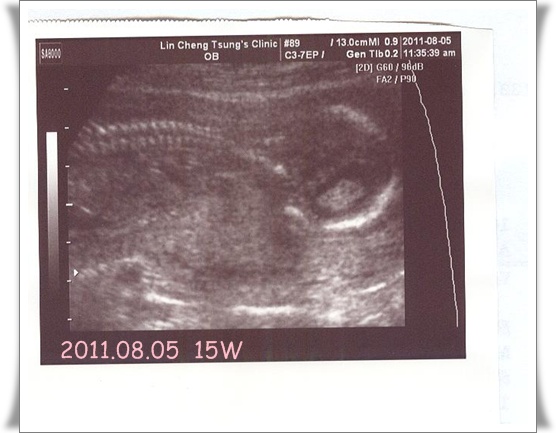

8/5又去產檢了,等了一個月再去看看我家二寶有沒有乖乖。

二寶今天剛好15週整。可以檢查中期唐氏症,所以今天麻麻被抽了一大管的血。

還好今天這個護士扎得夠狠,一針就見血。

不像上次那個幼嫰小護士把我當草人在那扎來扎去。想到就怕~